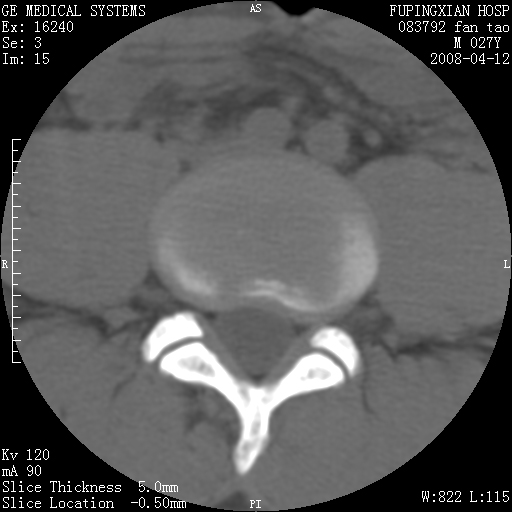

以下是引用前行在2008-4-13 13:53:00的发言:[br]椎间盘髓核终板下突出形成许莫氏结节及椎间盘突出,建议mr检查

以下是引用xclzq_910在2008-4-13 12:43:00的发言:[br]这个应该没什么了,椎间盘突出后反应性骨质吸收硬化.建议mr